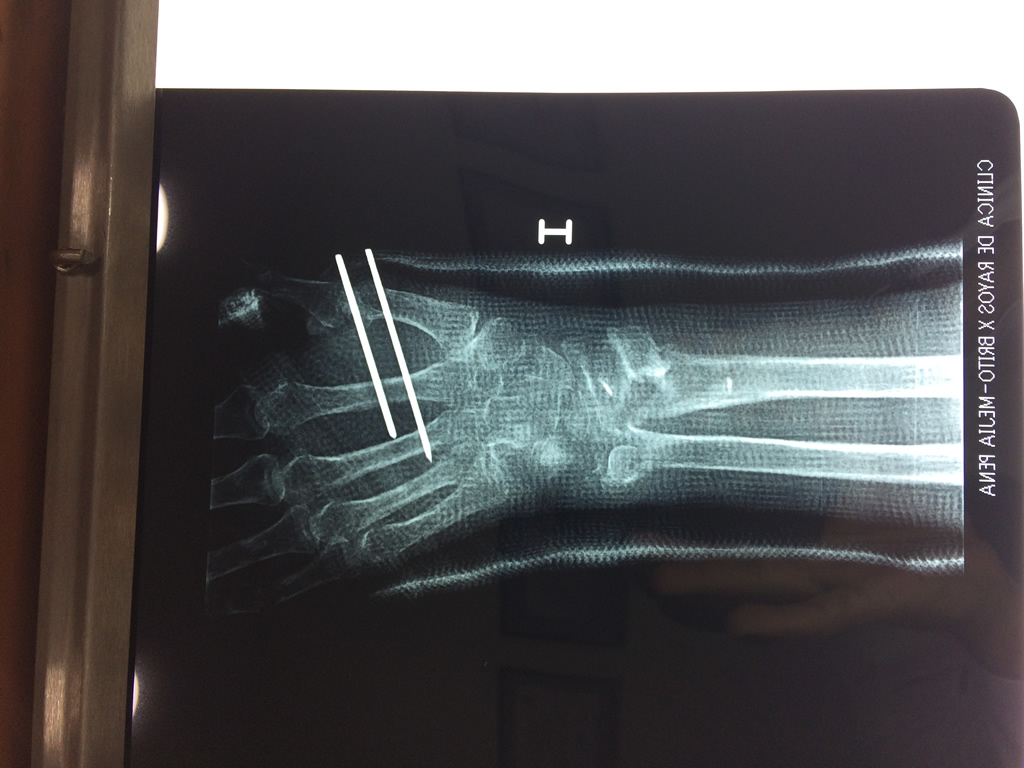

Cirugía de Fémur - Cirugías de Muñecas y Manos

Los procedimientos más comunes en cirugía de la mano son aquellos destinados a reparar traumatismos, incluyendo lesiones de tendones, nervios, vasos sanguíneos, y articulaciones; huesos fracturados; y quemaduras, cortes, y otros daños de la piel.